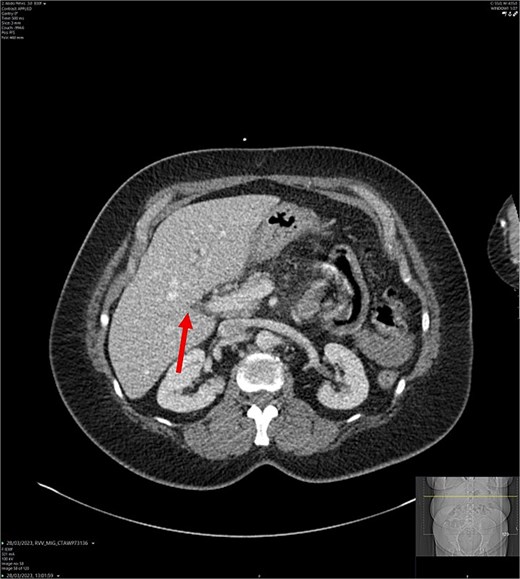

On admission, the patient’s blood tests showed normal inflammatory markers, liver function markers, and amylase (Table 1). The patient underwent an abdominal ultrasound scan, which did not visualize gallstones or the gallbladder. A computerised tomography (CT) abdomen-pelvis scan was done, and the gallbladder could not be visualized (Figs 1 and 2). Further investigations, which include a magnetic resonance cholangiopancreatography (MRCP) and hepatobiliary iminodiacetic acid (HIDA) scan, confirmed a gallbladder bud with an intact biliary tree (Figs 3–6). The patient denied a history of a cholecystectomy. She was diagnosed with gallbladder agenesis.

CT abdomen-pelvis scan in axial view. The arrow points to where we expect the gallbladder to be seen, but it cannot be visualized on the scan.